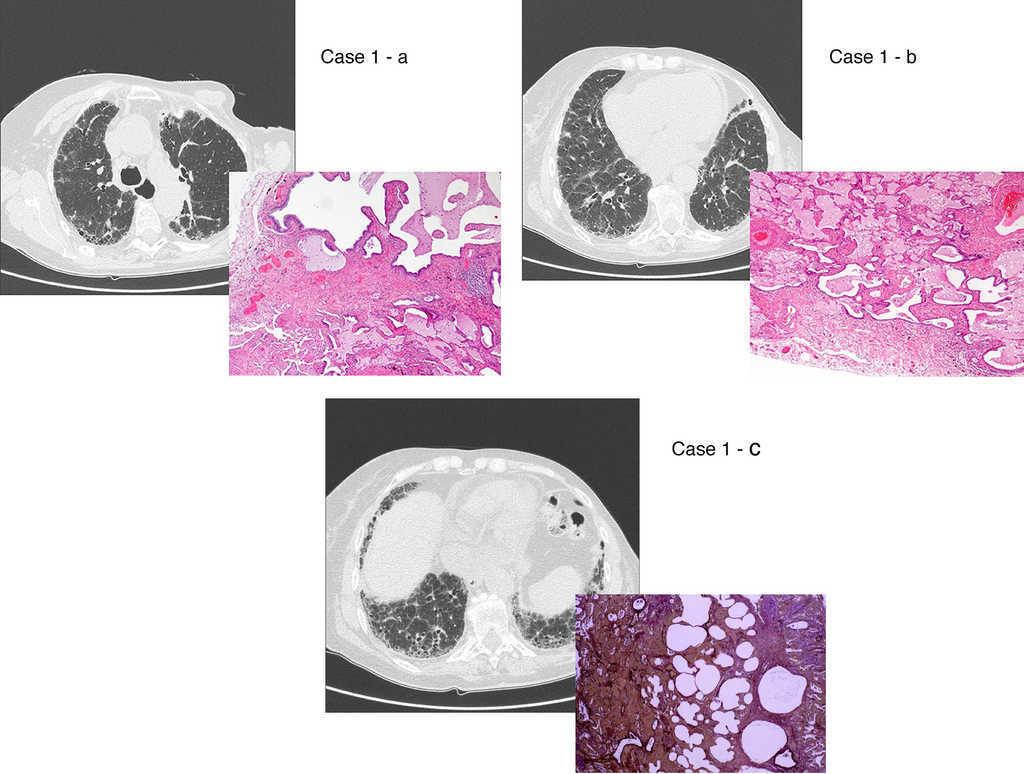

There are two aspects that may raise doubts in the HRTC interpretation: the distinction between honeycombing and traction bronchiolectasis and fibrosis with emphysema. The differential diagnosis is a challenge even for an experienced radiologist.47, 49, 50 The 2011 ATS/ERS/JRS/ALAT multidisciplinary consensus1 stated that the identification of four typical findings establishes the definite diagnosis of UIP: 1 – subpleural and basal lung lesions predominance; 2 – reticulation; 3 – honeycombing with/without traction bronchiectasis/bronchiolectasis; 4 – absence of findings that do not support a UIP pattern (Table 2, Table 3; Figure 2).

Figure 2. UIP/IPF identification in HRCT and histopathology. Case 1 – a: Common histopathological features of UIP/IPF consisting in honeycombing as a result of subpleural airway spaces confluence with bronchialization of epithelium where mucus cells may be predominant. HE 100×. Case 1 – b: The previous image aspects are revealed by higher production of mucus occupying the new formed subpleural smaller confluent airspaces. HE 100×. Case 1 – c: The interstitium intermingling honey-combing loses elastin fibres and is represented by fusiform cells, either fibroblasts or miofibroblasts, with collagen deposition. Elastin-van Gieson 100×. Case 2 – a: Irregular confluent air spaces with typical subpleural localization of UIP/IPF honeycombing with interstitium enlargement by fusiform cells. HE 100×. Case 2 – b: The adjacent lobular parenchyma accentuate histopathological heterogeneity, starting by overinflation and pseudo emphysema morphology. HE 100×. Case 2 – c: The lobular histopathological remodelling aspect of fibrosis enlarging alveoli septae till central bronchiolo-vascular axes and alveolar bronchialization. HE 100×. Case 3 – a: Small subpeural confluent air-spaces with bronchial-like epithelium and juvenile foci of fibroblasts in myxoid matrix; lymphocytes are seen. PAS 200×. Case 3 – b: UIP/IPF heterogeneous morphology in airspaces confluence with subpleural preponderance and committing the whole lobule. HE 100×.

The histological pattern of UIP must present: 1 – marked fibrosis/architectural distortion, with or without honeycombing in a predominantly subpleural/paraseptal distribution; 2 – patchy involvement of lung parenchyma by fibrosis; 3 – fibroblast foci; 4 – absence of features against a diagnosis of UIP suggesting an alternate diagnosis1, 51 (Figure 2).